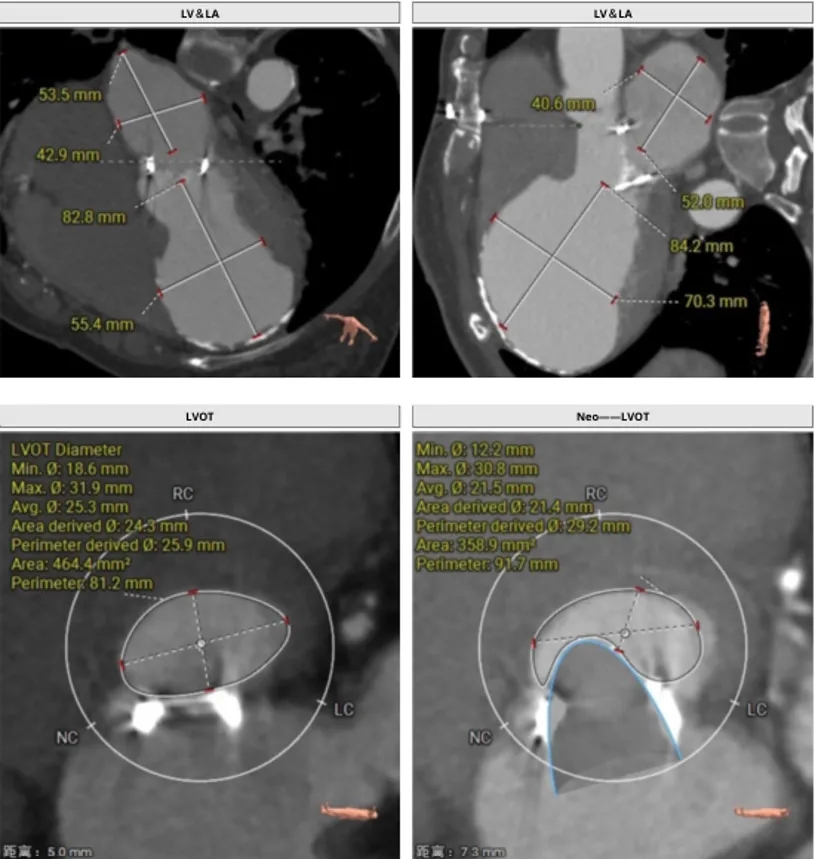

瓣架内径:24.0mm

瓣架外径:29.8mm

心室侧2mm:23.8mm

心室侧4mm:23.2mm

LVOT:464.4mm²

neo-LVOT:358.9mm²

左室心尖内壁钙化

瓣架高度:19.4mm

投照角度:RAO42°,CRA49°